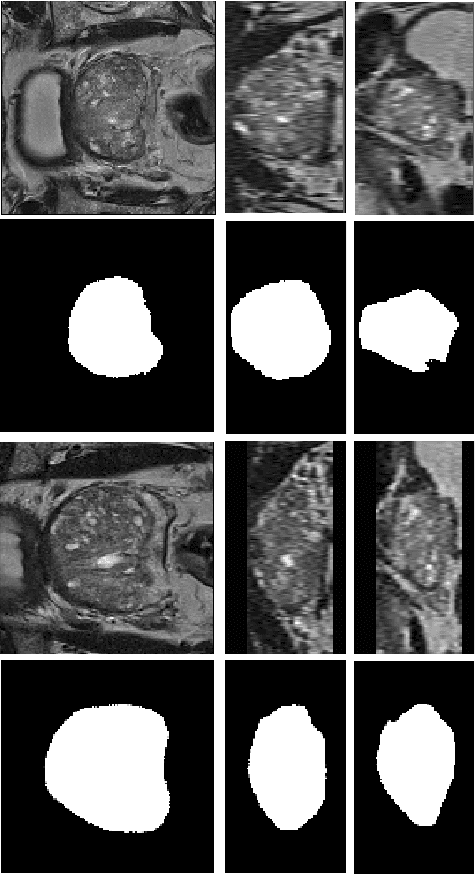

Abstract:We propose a novel automatic method for accurate segmentation of the prostate in T2-weighted magnetic resonance imaging (MRI). Our method is based on convolutional neural networks (CNNs). Because of the large variability in the shape, size, and appearance of the prostate and the scarcity of annotated training data, we suggest training two separate CNNs. A global CNN will determine a prostate bounding box, which is then resampled and sent to a local CNN for accurate delineation of the prostate boundary. This way, the local CNN can effectively learn to segment the fine details that distinguish the prostate from the surrounding tissue using the small amount of available training data. To fully exploit the training data, we synthesize additional data by deforming the training images and segmentations using a learned shape model. We apply the proposed method on the PROMISE12 challenge dataset and achieve state of the art results. Our proposed method generates accurate, smooth, and artifact-free segmentations. On the test images, we achieve an average Dice score of 90.6 with a small standard deviation of 2.2, which is superior to all previous methods. Our two-step segmentation approach and data augmentation strategy may be highly effective in segmentation of other organs from small amounts of annotated medical images.